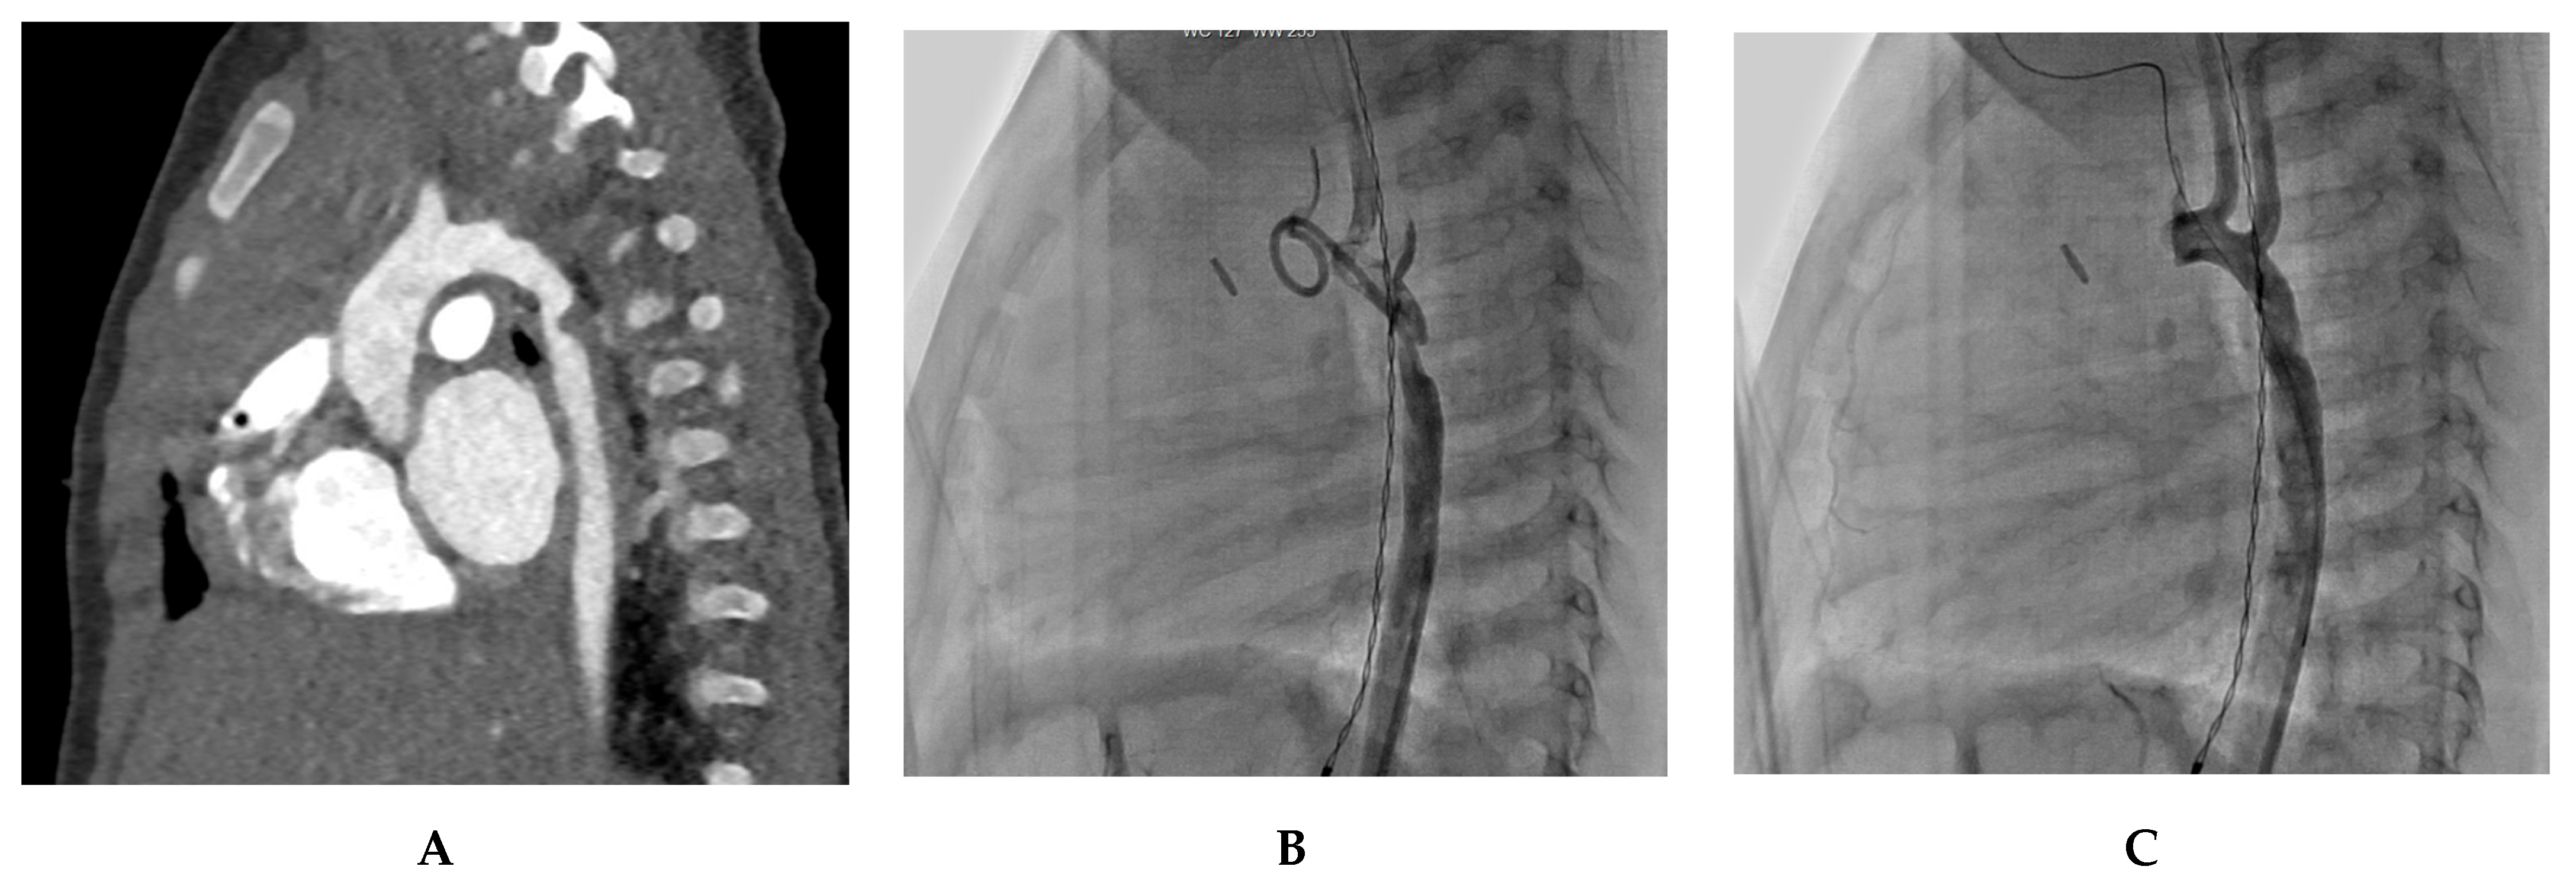

7. Our Experience-Case Series